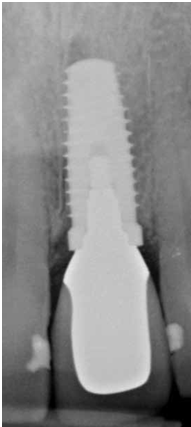

患者的原始片 91/06/13

患者陳先生於91/06/03初診,為一個牙周病患者,合併有右下缺牙。經過保守性牙周處理後,於91/08/14放置右下三顆植體。

完成後大約半年至一年進行一次例行性追蹤檢查,並無特別問題。以下為96/08/13時的追蹤小片,可以見到當時三顆植體的骨高度並無顯著變化。但右下第一小臼齒此時發現有搖動度增加的情形,當時對該顆牙做了咬合調整,降低咬合功能負荷,希望能有所改善。

96/08/13

患者之後於96/11/08在右下第一小臼齒與植體間有膿胞產生,並於97/02/21確認右下第一小臼齒有根裂的情形,因此在97/02/29拔除此牙;經過將近半年後,於97/09/23放置一顆植體於此位置

97/02/21 確定根裂時拍的片子

97/02/21

97/09/18 拔牙半年後安排右下第一小臼齒植牙前

97/09/23 右下第一小臼齒植牙完成時

98/01/08經過三個半月做右下第一小臼齒的二階暴露,發覺鄰牙的植體高度竟已掉下來